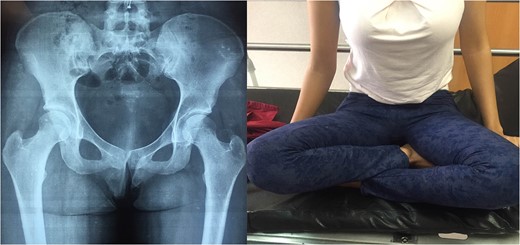

1: Patient with hip flexion and internal rotation and X-ray with traumatic bilateral posterior hip dislocation.